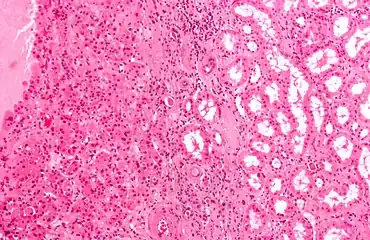

Micrograph of a renal oncocytoma, a type of benign kidney tumour. H&E stain. | |